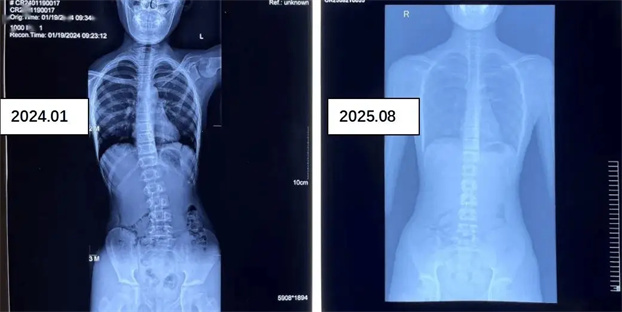

参加康复医学科脊柱侧弯训练营青少年前后对比照

通过调整优化关节和肌肉失衡问题,实现脊柱冠状面、水平面和矢状面的三维生物力学矫正,以及脊柱稳定性强化训练帮助脊柱恢复直立。系统康复治疗,可减小脊柱侧弯角度,显著改善临床症状。